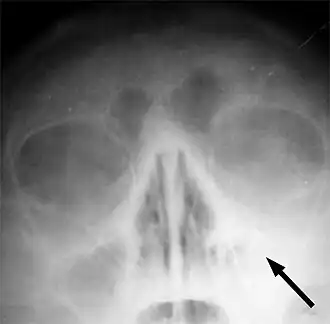

![]() Рентгеновский снимок пазух больного гайморитом (стрелкой обозначено затемнение в области верхнечелюстной пазухи, указывающее на присутствие в ней жидкости) | |

Одним из основных симптомов гайморита является тянущая боль, которая возникает при наклоне туловища вперёд. Подтверждение диагноза производится на основании рентгеновского снимка.